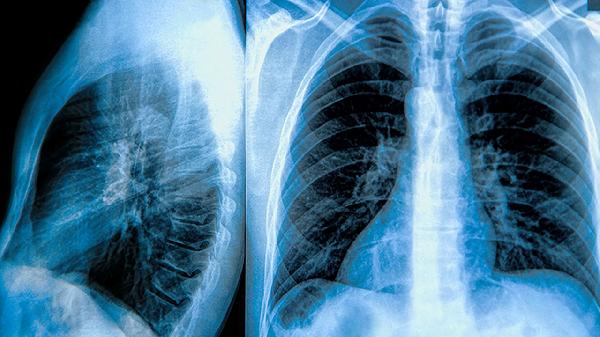

肺气肿和肺大泡患者需谨慎使用补肺丸,建议在医生指导下评估个体情况后决定。补肺丸作为中成药,主要成分含党参、黄芪等补益类药材,适用于肺气虚证,但肺气肿的病理基础为肺泡结构破坏,肺大泡存在破裂风险,二者均需以西医规范治疗为主。

肺气肿首选长效抗胆碱药如噻托溴铵联合β2受体激动剂如福莫特罗。肺大泡直径超过3厘米或反复感染者,需考虑胸腔镜肺大泡切除术或肺减容手术。

肺气肿患者日常需坚持腹式呼吸训练,采用低糖高蛋白饮食维持呼吸肌功能,避免粉尘刺激。肺大泡患者禁止潜水、高空飞行等气压变化活动,剧烈运动可能诱发气胸。冬季注意接种肺炎疫苗和流感疫苗,急性感染需及时使用抗生素。定期复查肺功能与胸部CT评估病情进展,任何新发胸闷或突发胸痛需立即就医。